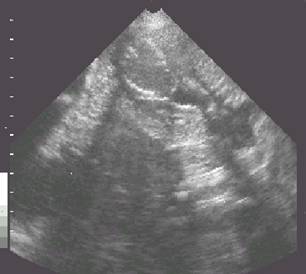

Pregnancy fetal vesicles at 28 days.

It is essential to visualize the fetus within the vesicle.